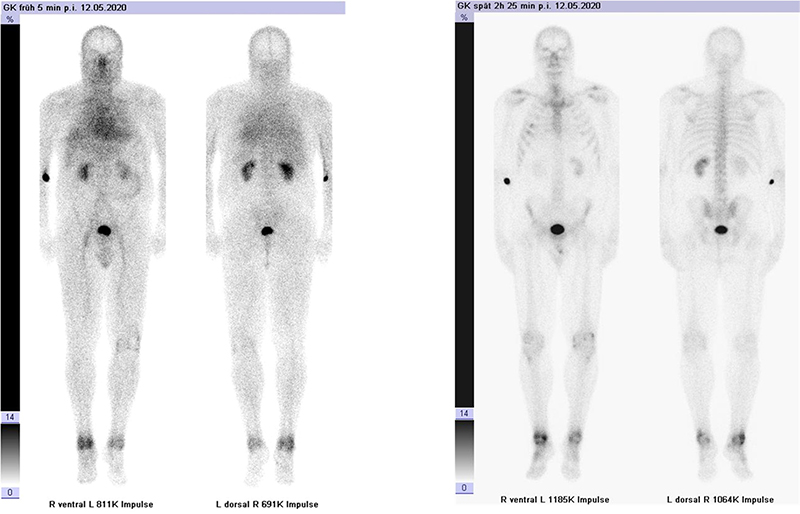

Abbildung 1.8.a und b: Akute Arthritis bei bekannter Gicht in beiden OSG: links die Früh-/Weichteilphase; rechts die Mineralisations­phase. Deutliche, entzündlich bedingte Mehranreicherungen in der Früh-/Weichteilphase. In der Mineralisation­sphase erkennt man die entzündliche Mitreaktion der subchondralen Gelenkabschnitte.

Zum Lesen der Bildbeschreibung und zur Vollansicht bitte das Bild anklicken. Bild: H. C. Rischke

Abbildung 1.8.c - e: Akute Arthritis in beiden OSG, rechts > links. Im SPECT/CT erkennt man die Mitreaktion der subchondralen Gelenkabschnitte. Die Arthritis ist so akut, dass (noch) keine ossären morphologischen Veränderungen im CT abgrenzbar sind.

Zum Lesen der Bildbeschreibung und zur Vollansicht bitte die Bilder anklicken. Bilder: H. C. Rischke